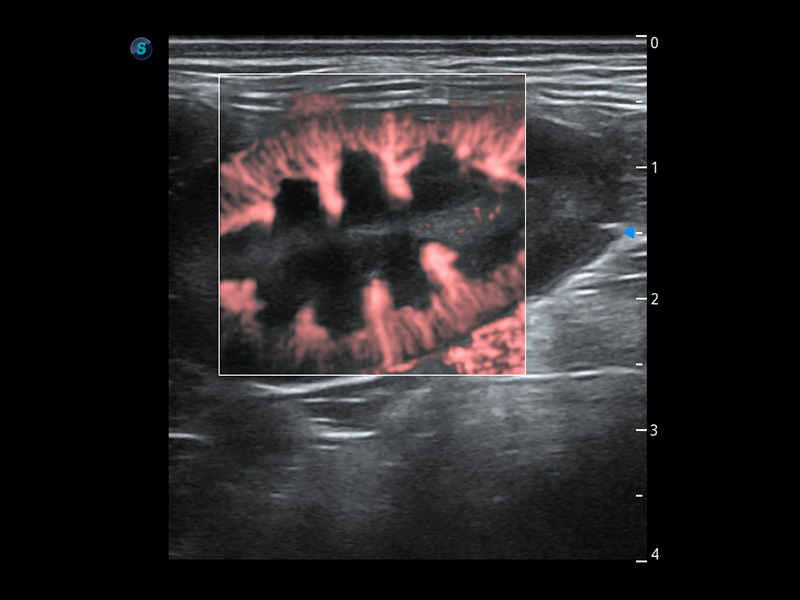

PDI 能量多普勒血流

提供高灵敏度和空间分辦率的血流图像,获得更加真实和丰富的诊断信息。

优异的基础图像

(犬)胆囊泥沙